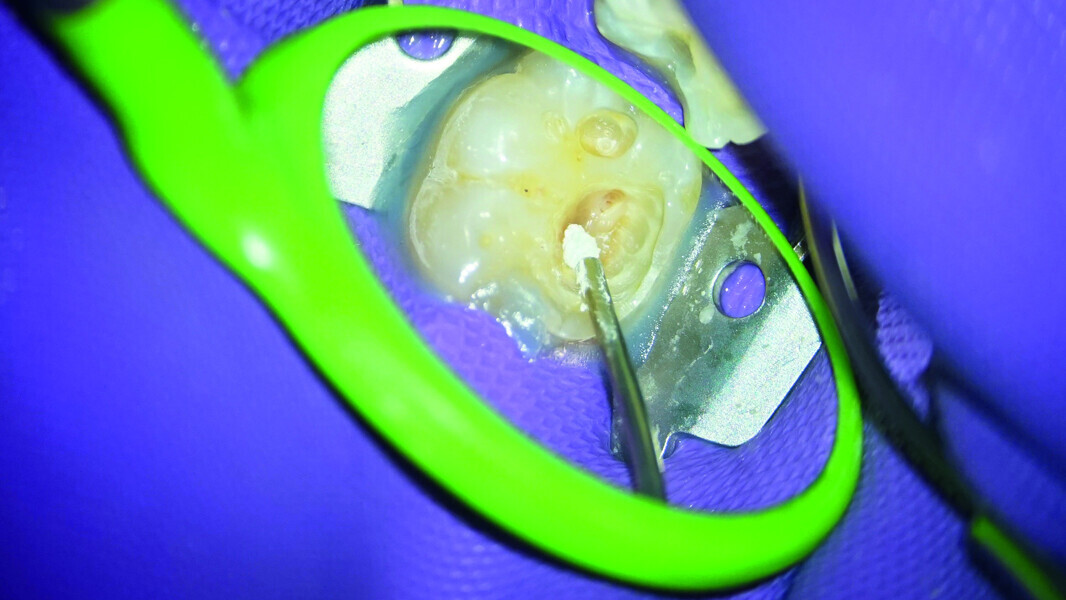

Direct pulp capping as a conservative procedure to maintain pulp vitality